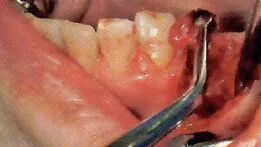

3 切开

利用手术刀·电刀等器械将手术区域的牙龈切开

医生利用手术刀进行切开。首先避免吸唾器在手术刀的切开路线上阻碍医生的操作。切开线设计分为三角形,四边形和沿牙龈缘等各种不同的形状。口腔卫生士一定要事先与医生确认切开设计的形状。

切开线设计(有残根的情况)

务必保证切开线区域的视的野晰度(切开前要吸引唾液,切开过程中要吸引血液)

切开前,一定要将切开线区域的唾液吸引干净。如果切开区域有唾液残留的话,会造成医生无法找到切开线路。切开时,从切开线区域会有血液溢出。将吸唾器放置到出血点,正确找到出血点才能更加有效的将溢出的血液吸引干净。